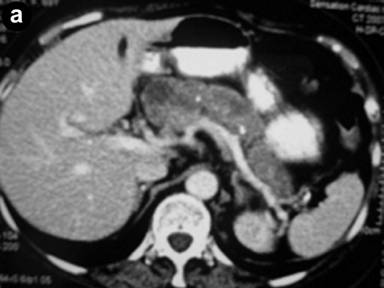

A 70-year-old lady, with a 15-year history of chronic pancreatitis initially presented with persistent abdominal pain, nausea and steatorrhea. She was a non smoker with modest alcohol consumption and had a first degree relative with a history of pancreatitis. During exacerbations serum amylase and lipase were elevated. Gallstone disease was never identified. Over time the patients’ main symptoms evolved into weight loss and chronic abdominal pain with CT and MRI imaging showing signs of fibrotic changes to the pancreatic gland with minimal calcification. Aside from the family history, there were no other clear identifiable causes for her chronic pancreatitis. She had attended regular review under the physicians but presented acutely to the emergency department with an acute exacerbation of epigastric pain, fatigue and weight loss. She proceeded to have a CT and an MRI scan which revealed a non-homogeneous cystic mass in the head of pancreas with maximum transverse diameter of 4.4 cm, suspicious for a malignant tumor (Figure 2a). These findings were not present on scans performed two years earlier. The pancreatic cyst was in communication with a clearly dilated main pancreatic duct. The imaging findings were compatible with the diagnosis of an IPMN and surgical resection was decided. Intraoperatively widespread extensive microcystic lesions and fibrotic alterations were demonstrated throughout the pancreas and a total pancreatectomy was deemed the most appropriate surgical option (Figure 2b).

Figure 2. Radiological, intraoperative and histological findings of Case #2. a. Abdominal computed tomography showed non-homogeneous cystic mass in the head of pancreas. b. Intraoperative findings of the total pancreatectomy and splenectomy specimen. c. Histological slide showing cystic areas with IPMN features and adjacent solid areas with multiple glands and tubules resembling usual ductal adenocarcinoma. |